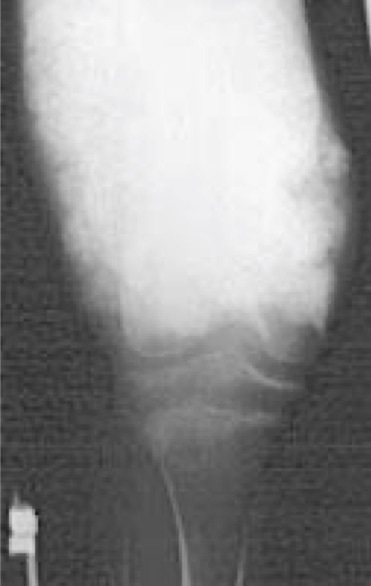

Osteoid

Malignant osteoid can be recognized radiologically as cloud-like or ill-defined amorphous densities with haphazard mineralization

Pattern is seen in osteosarcoma